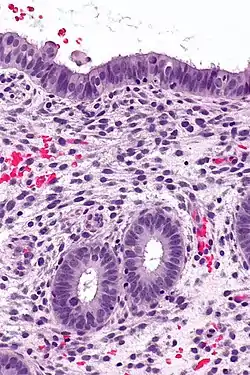

The endometrium consists of a single layer of columnar epithelium plus the stroma on which it rests. The stroma is a layer of connective tissue that varies in thickness according to hormonal influences. In the uterus, simple tubular glands reach from the endometrial surface through to the base of the stroma, which also carries a rich blood supply provided by the spiral arteries. In women of reproductive age, two layers of endometrium can be distinguished. These two layers occur only in the endometrium lining the cavity of the uterus, and not in the lining of the fallopian tubes.[4][5]

(A) proliferative endometrium (Left: HE × 400) and proliferative endometrial cells (Right: HE × 100)

(B) secretory endometrium (Left: HE × 10) and secretory endometrial cells (Right: HE × 10)